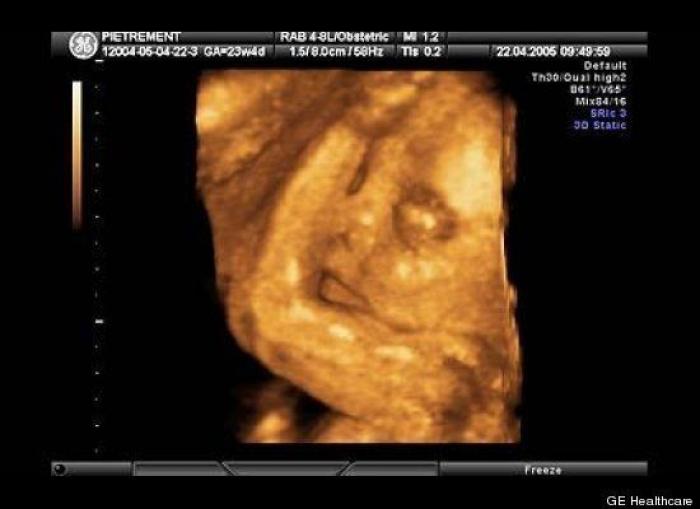

En esta galería puedes ver en fotos como es el desarrollo de un feto de semana en semana:

Desarrollo del feto, en fotos